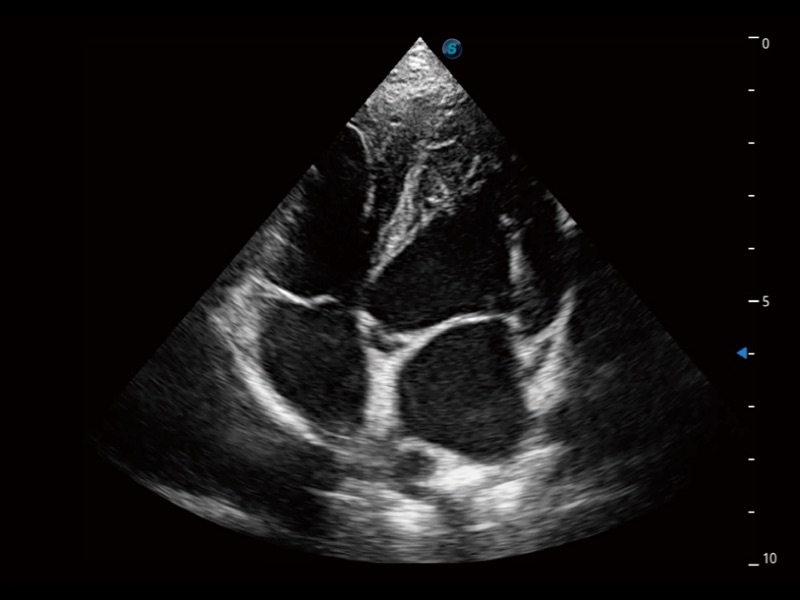

能够基于左心室壁追踪和辛普森法,自动计算射血分数,支持多个可移动点描迹,与手动测量相比,极大节省了动物医生的时间和精力。

当心脏测量结果超出正常范围时,可实时预警提示动物医生,减少疾病漏诊概率。